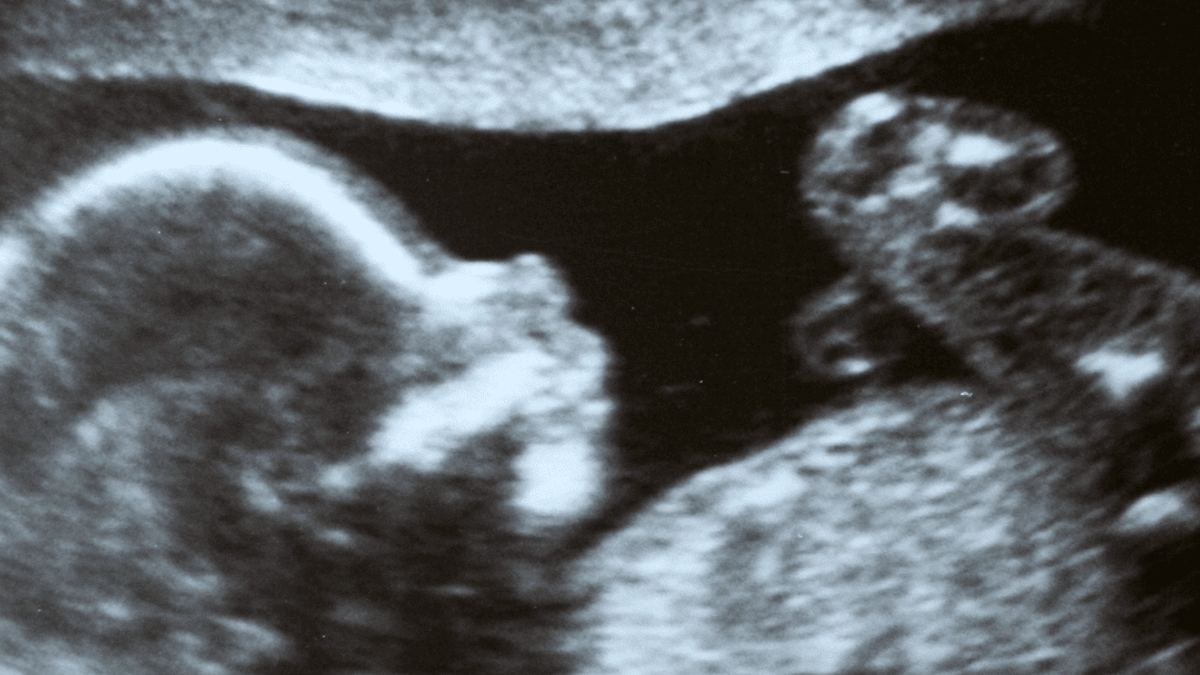

Op 22 januari toen de pijnmedicatie op de eerste hulp de scherpe randjes van de pijn niet wegnam, en ze zagen hoe ik ten einde raad was, hebben ze besloten op de scan van m’n buik te maken die schadelijk was voor de baby. Ik lag nog geen twee minuten in die smalle buis om de scan te maken en ik werd eruit gehaald.

Mijn hoofd tolt ik raak in paniek. Ik dacht dat er iets mis was met de baby. De baby die in mij groeide, die ik nog maar moeilijk kon accepteren. Ik bel mijn moeder op en zij komt naar het ziekenhuis. Nog voordat m’n moeder gearriveerd was, stonden de chirurgen al in de kamer met de mededeling dat ik met spoed geopereerd moest worden, want er zaten meerdere knopen in m’n darmen. Met de baby is alles goed.